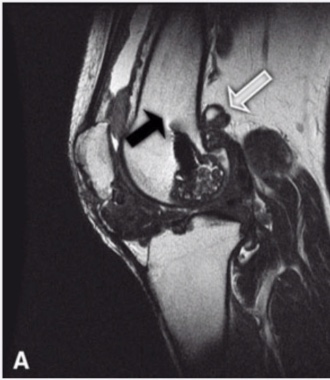

在MRI的影像之中,腱鞘巨細胞瘤最大的特色,便是腫瘤中因為富含大量的血鐵素(hemosiderin),因此在T1與T2訊號中,均會呈現特殊的低訊號,這個特色,使用來區分腱鞘巨細胞瘤與其他的良性或是惡性腫瘤的重要指標。以下為一位46歲男性膝蓋腱鞘巨細胞瘤的影像學表現:

46歲男性,右膝腱鞘巨細胞瘤(MRI)

58歲女性,左髖腱鞘巨細胞瘤(MRI)